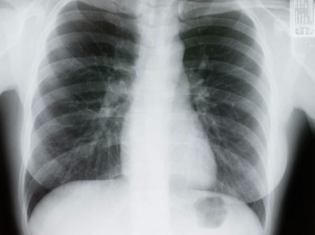

(RxWiki News) Living beyond lung cancer is generally tied to the stage at which it’s detected. But what if survival rates weren’t tied to time of diagnosis, but rather where you lived?

Researchers have found that lung cancer survival times varied widely in six developed countries. This difference couldn't be explained by the timing of diagnosis only. Treatment access and quality and other factors also apparently played a role.

Non-small cell lung cancer is the most common and treatable form of the disease, accounting for 80 percent of all cases. Small cell lung cancer tends to be more aggressive. This study involved patients with both types.